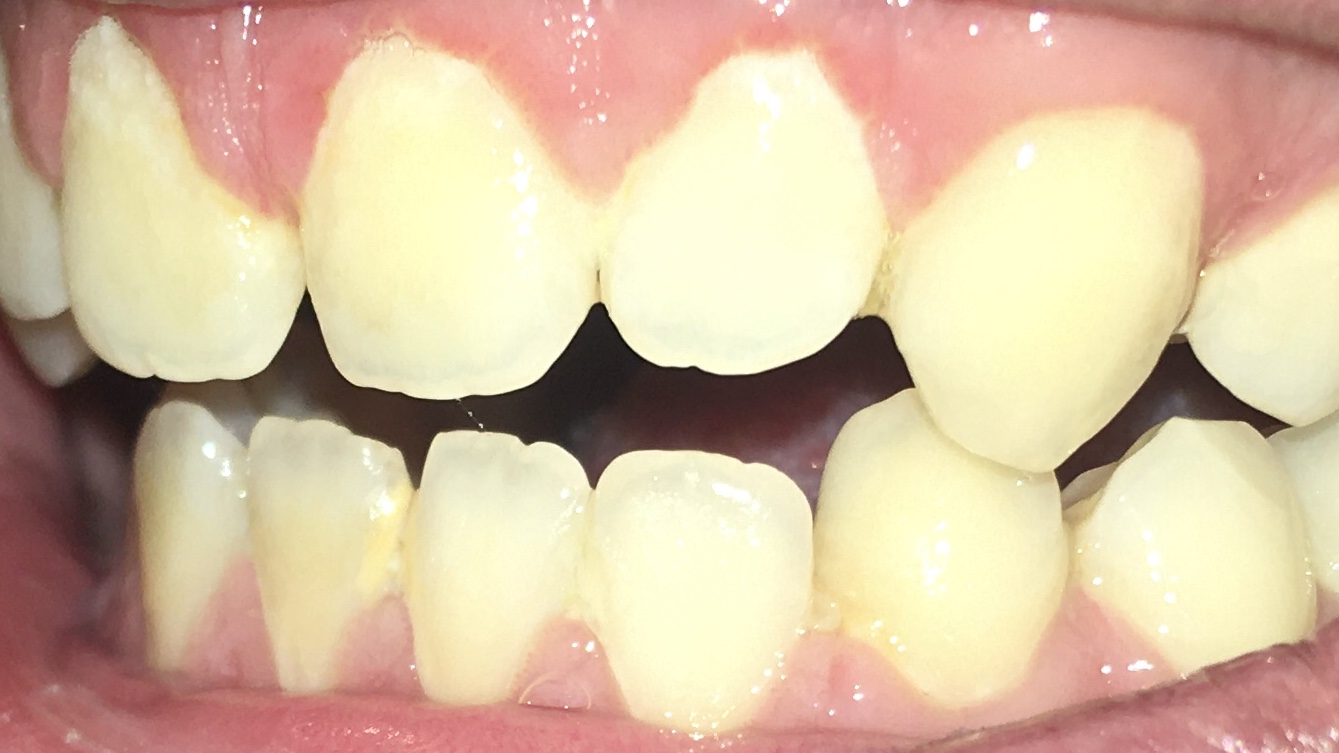

Аноны, а дорого ли и вообще возможно починить вот такой клиновидный деффект? Фото не мое, но один в один. Заупустил я зубы, а теперь боюсь, что потеряю